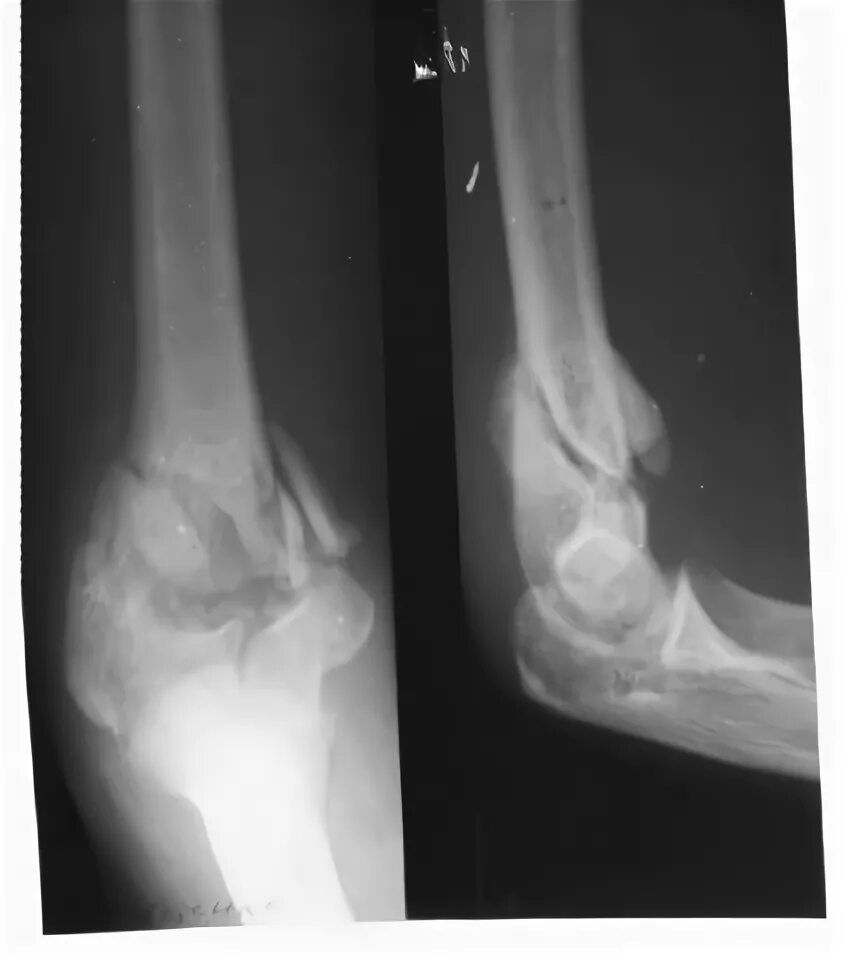

Оскольчатый перелом плеча со смещением